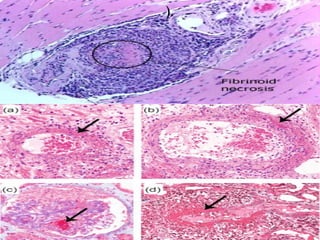

Morphology

 Segmental fibrinoid necrosis of the

media with focal transmural

necrotizing lesions

 In some areas (typically postcapillary

venules), only infiltrating and fragmenting

neutrophils are seen giving rise to the term

Leukocytoclastic vasculitis

skin biopsy samples revealing leukocytoclastic

vasculitis with extensive fibrinoid necrosis

within dermal capillaries

Fibrinoid necrosis destroying the vessel wall

with extravasation of red blood cells and nuclear

debris in the adjacent areas

).